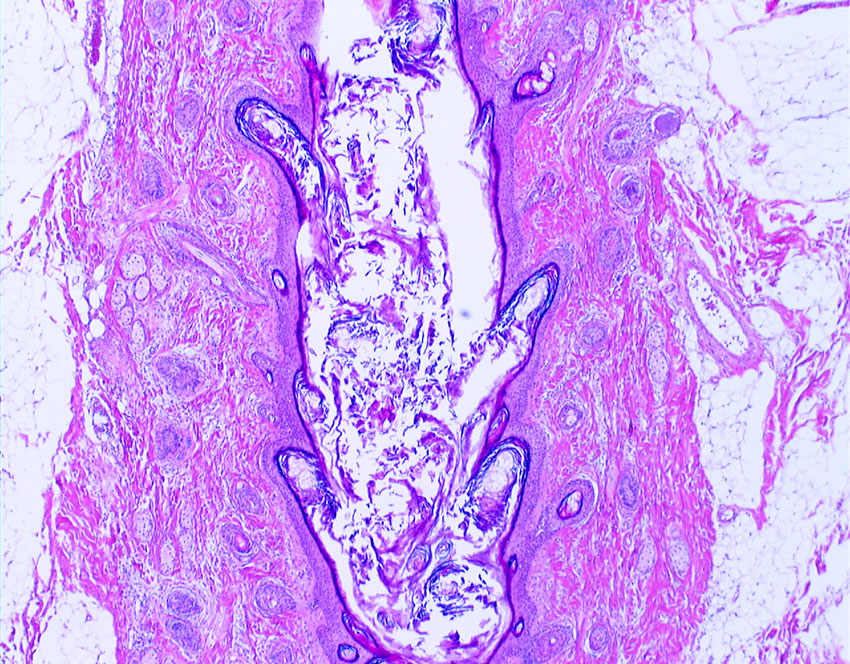

照射後の奇形腫の病理像

左上にはcartilage,右上にはkeratin squamous tissueがみられます。左下は繊維生組織のみdense collagenous tissueです。

生検術で胎児性癌と未熟奇形腫の混合型と診断されたために,化学療法と61.1グレイの放射線治療がなされていました。しかし,大きな松果体腫瘍が残り全摘出したものです。この子の腫瘍は治っていて元気に暮らせています。

奇形腫の照射後はいつもそうなのですが,dense collagenous tissueとfibroblastic spindle cellが組織の主体となっています。要するに肉芽腫のようなものです,ですから,手術摘出ではものすごく硬い線維性の腫瘍となっていてハサミでも切れずに難渋します。出血もしないし脳とは剥離できるのできます。放射線化学療法前の生検による組織像(悪性要素)は消失して単なる成熟奇形腫との病理診断となってしまいます。しかし,この組織のどこかに悪性度の高い細胞が潜んでいて,播種再発するなどということも経験しました。放射線治療後の病理組織診断はその後の予後の予想のためには役に立ちません。